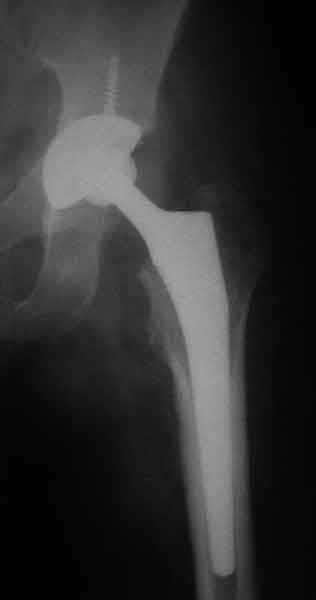

Насчет 8 см согласен с А.Н. Челноковым, это наверное ортопедическое за счет приводящей, сгибательной контрактуры и, возможно, колена. на ликвидацию укорочения у нас обычно уходит около 2-х нед. снимки в приложении, возможно не очень показательные, но других с ходу не нашел, завтра еще поищу.